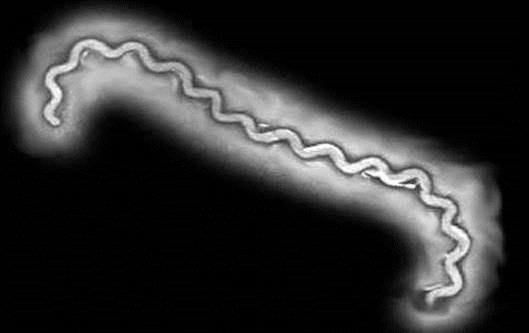

Лептоспиры: фотографии удивительных микроорганизмов